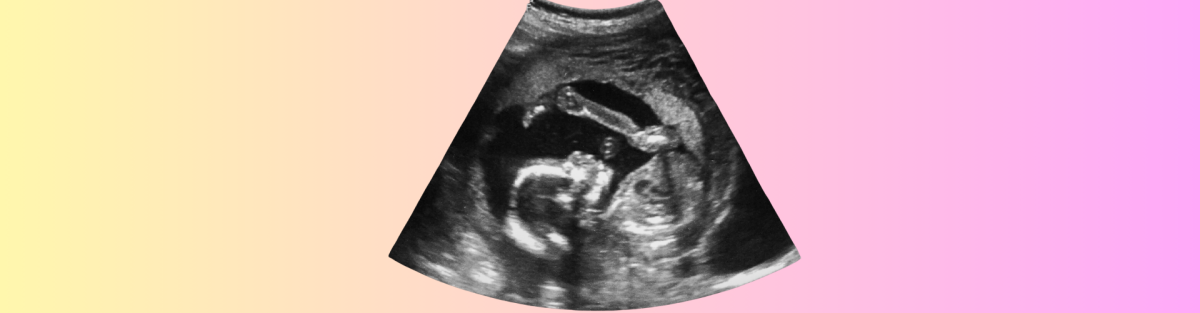

Kadın doğum uzmanları, bebeğin pozisyonunu anlamak için manuel muayene yapabilir veya ultrasonla değerlendirme isteyebilir. Ultrason, bebeğin başının hangi yöne baktığını kesin olarak belirlemek için etkili bir yöntemdir.